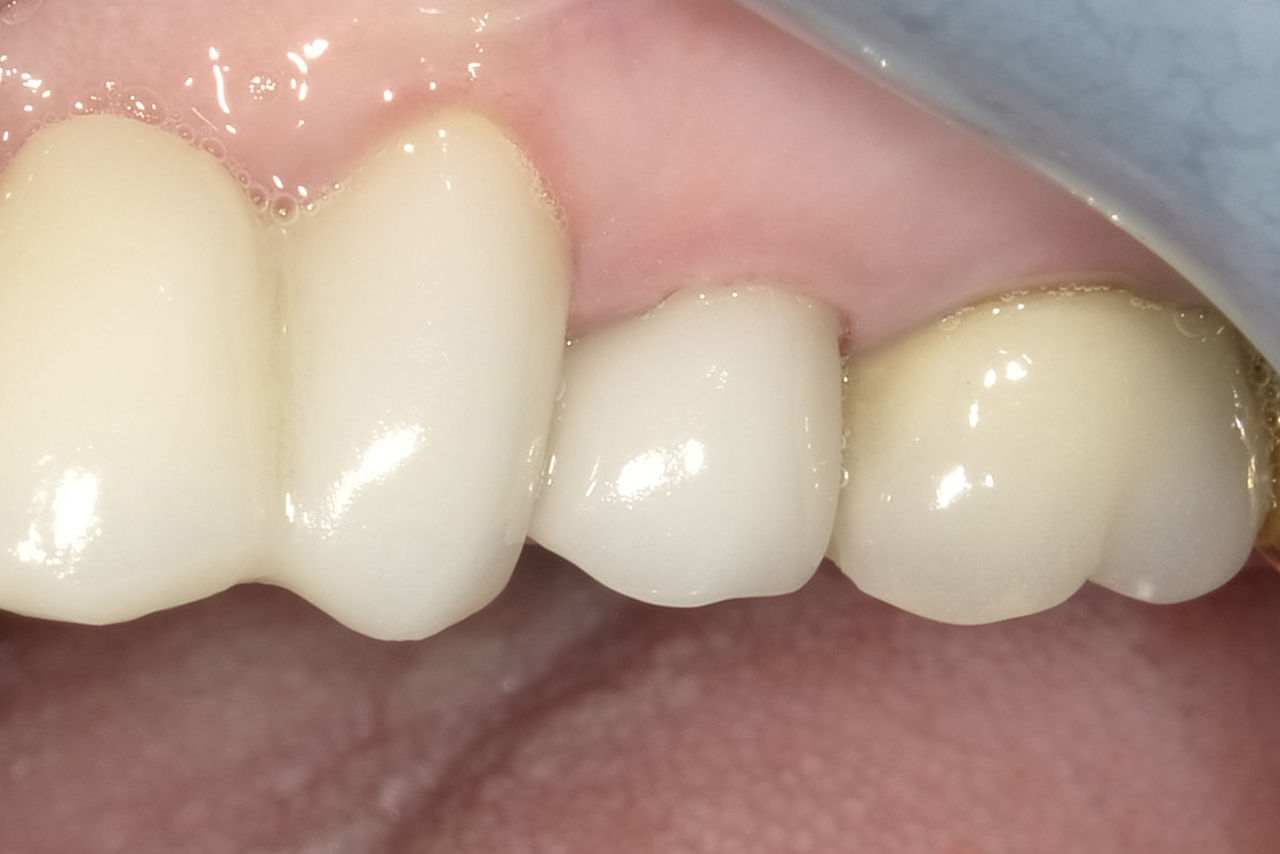

First upper molar, in 90 minutes

Katana Zirconia STML single crown

CEREC Primemill not only brings speed to the appointment, but also versatility in milling strategies. In this case we chose the Extra Fine milling mode to achieve maximum esthetics and attention to details as possible.

Before: Fractured metal-ceramic crown on tooth 14, which had previously been treated endodontically.

After: Translucent full zirconia crown for an esthetic result with maximum resistance and retention shape.